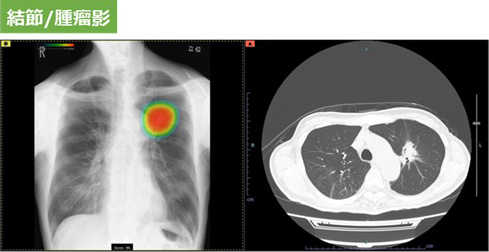

撮影した胸部レントゲン画像を自動解析して病変が疑われる領域を検出し、その部分をハイライトします。その領域を医師が再確認することで、見落し防止を支援します。

肺疾患の主要な画像所見となる「結節・腫瘤影」、「気胸」、「浸潤影」を検出することができます。